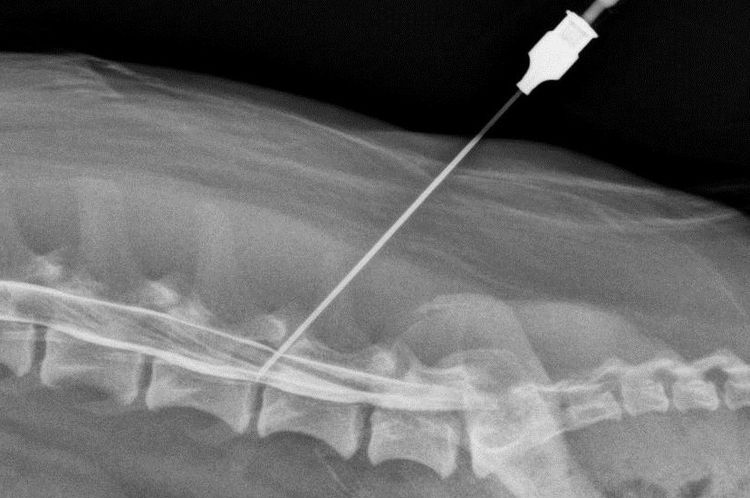

Un vétérinaire établit un diagnostic préliminaire de compression nerveuse en se basant sur les symptômes décrits par le propriétaire du chien et sur les résultats de l'examen neurologique. Déterminer la zone exacte de la lésion et évaluer sa gravité peut s'avérer difficile, car la douleur associée à une compression nerveuse est diffuse. Afin de déterminer la localisation de la compression et la profondeur du trouble de la conduction nerveuse spinale, des techniques d'imagerie diagnostique sont utilisées. Il peut s'agir d'une imagerie par résonance magnétique (IRM) ou d'une myélographie (radiographie avec injection d'un produit de contraste sous la moelle épinière). Ces examens permettent de détecter les zones de compression médullaire ou la présence de déformations de la colonne vertébrale.